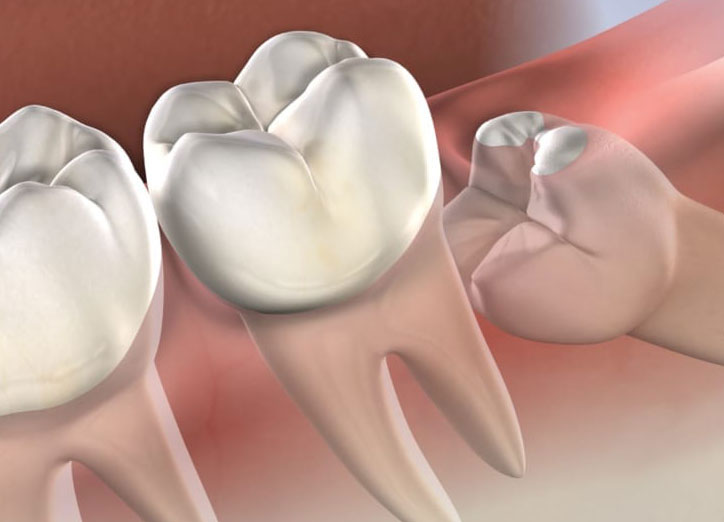

The gum overlying the tooth may get infected causing severe pain and discomfort radiating to the jaws, ear, temple region. The wisdom teeth, if they erupt in an abnormal position cause changes in the temporomandibular joint leading to problems over a period of time and also can damage to the adjacent teeth. The abnormal position of the teeth may cause difficulty in brushing and maintaining good hygiene of the teeth.